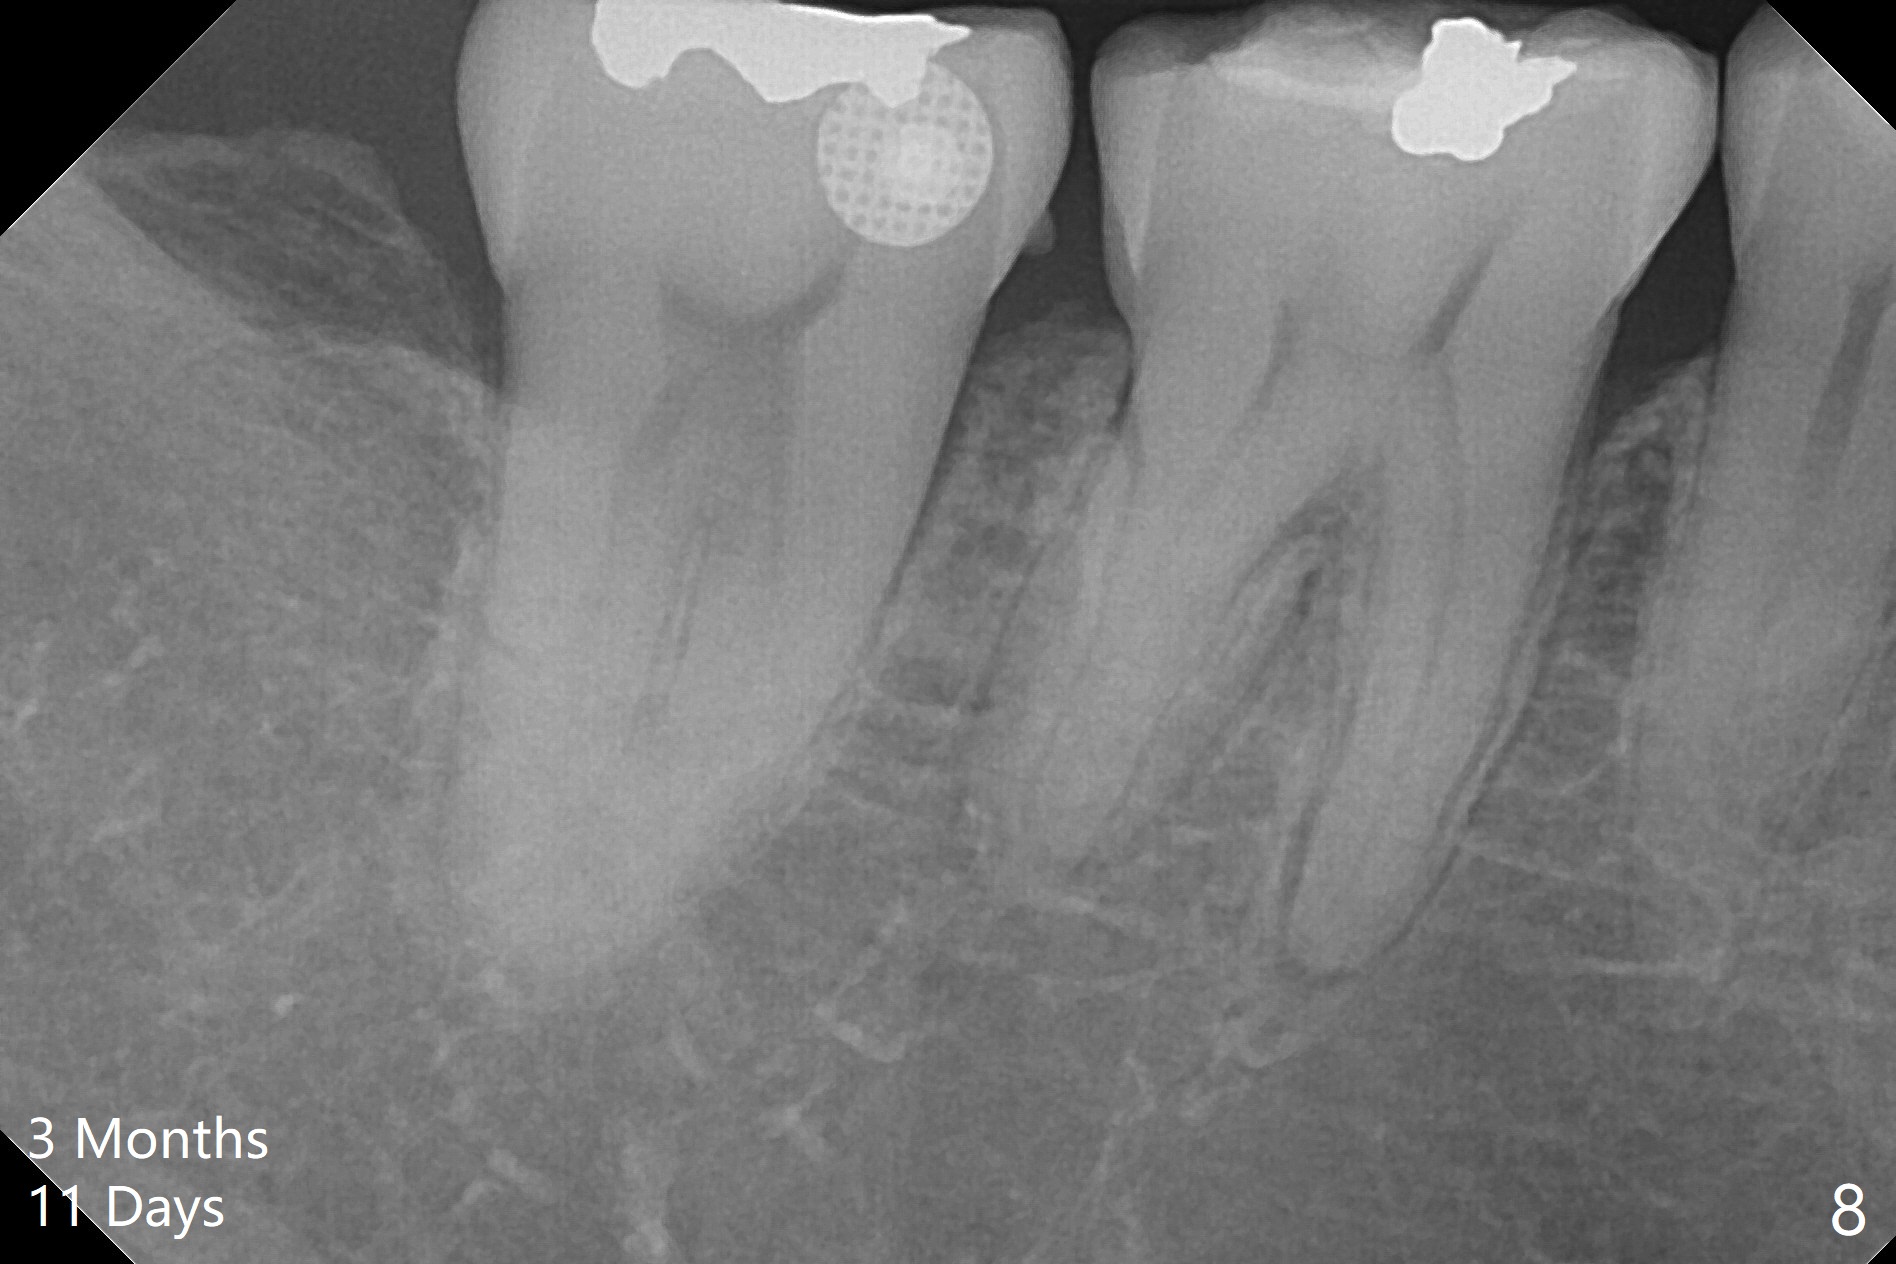

A 51-year-old woman agrees to correct cross bite of R7s 10 years post UR6 crown (Fig.1,2). Composite is placed in LR6 (Fig.3 C) and LL7 for clearance. Lingual buttons are placed in the buccal surface of UR7 (Fig.3 <) and lingual surface of LR7 (Fig.6 ^) with 6 oz. elastic in between. Cross bite correction finishes in 3 months. Photos (Fig.4-6) and PAs (Fig.7,8) are taken 11 days post orthodontic treatment.